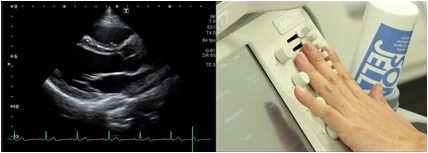

Adjustment of gain

Gain is used to adjust the sensitivity of the received echoes. Noise will appear in the entire image if the gain is too high. If the gain is too low, information will be missing from the image.